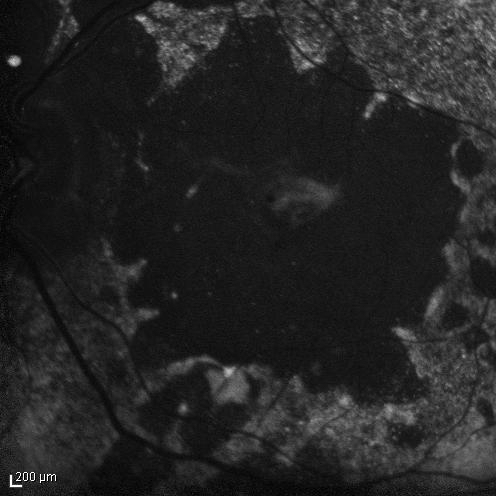

Figure 7: Index patient, OCT Spectralis EDI in 2011, at age 48. Note dilated choroidal vessels and a thick choroid, and cystic degeneration of the retina, with reduced thickness of the retina compared to previous recordings.

External examination of the eyes was normal, including corneal size (11 mm diameter OU) and palpebral fissure (Figure 1 [Fig. 1]). BCVA was 20/32++ in the RE and 20/200 in the LE (correction RE sph +5.25 cyl +1.50 axis 42 and LE +5.50 cyl +0.75 axis 109). Ocular tension was 17 mmHg RE and 18 mmHg LE. Biomicroscopic examination showed in both eyes a mildly reduced anterior chamber depth and a maculopathy (Figure 2 [Fig. 2]). Fluorescein angiography confirmed the presumed diagnosis of CSC OU with macular serous detachment, diffuse pigment epitheliopathy, and mild focal subretinal leakage (Figure 3 [Fig. 3]). Focal lasercoagulation was performed in the RE in 1995, 1996, 1997 and 1998, but despite this treatment the macular detachment increased slowly and cystic retinal degeneration and fibrosis became evident, as well in the RE as in the LE (Figure 4 [Fig. 4]). Repeated FA revealed progressively expanding subretinal lesions in the posterior pole of both eyes, with leakage, staining and pooling of fluid (Figure 5 [Fig. 5]). In 2004, PDT was available, and as the exudative lesions were pronounced, one session of SFR PDT was administered in the LE, however, without benefit. Over the last years of follow-up eye drops with dorzolamide were used, apparently without benefit. OCT was available in 1997, and repeated scans showed pronounced and progressive cystic degeneration of the macula OU (Figure 6 [Fig. 6]). EDI OCT, available in 2011, demonstrated dilated choroidal vessels and a thick choroid (Figure 7 [Fig. 7]). ICGA also showed dilated choroidal vessels (Figure 8 [Fig. 8]). Ultrasound A-scan biometry demonstrated OU reduced total axial length, reduced anterior chamber depth, reduced vitreous cavity and increased lens thickness (Table 1 [Tab. 1]). Recently, atrophic changes became evident (Figure 9 [Fig. 9]) and on OCT decreased retinal thickness was observed (Figure 7 [Fig. 7]). Autofluorescence imaging showed large areas of hypoautofluorescence compatible with afunctional retinal pigment epithelium and retina (Figure 10 [Fig. 10]). VA in 2011 was 20/800+ in the RE and 20/600 in the LE.